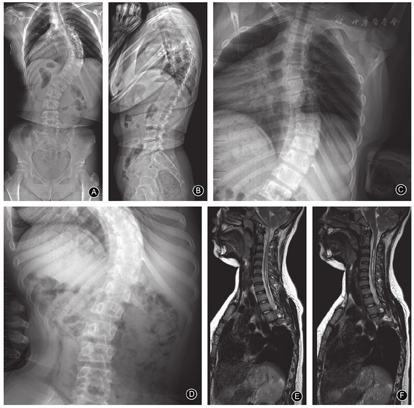

儿童组的主弯Cobb角为31.1°±11.9°(图3)、青少年组为56.7°±17.0°(图4)、成人组为70.7°±22.6°(图5),随着年龄增加,主弯Cobb角明显增大,三组的差异有统计意义(P< 0.001,表2);主弯柔韧性明显降低(63.9%±28.7% vs 43.8%±20.0% vs 36.9±22.7%,P=0.044,表2);次弯Cobb角明显增大(16.8°±8.8° vs 34.8°±14.7° vs 41.6°±17.2°,P< 0.001,表2)。

青少年组CB为(9.9±7.5)mm,优于儿童组(15.6±13.3)mm和成人组(18.7±14.9)mm(P=0.007,表2)。三组发生冠状面失衡的患者分别为2例、1例和3例。各组间主弯AVT的差异则无统计学意义(P=0.192,表2)。

儿童组、青少年组和成人组患者的TK(32.1°±8.0° vs 32.5°±12.9° vs 43.3°±20.9°,P=0.017,表3)、LL(50.4°±9.3° vs 54.6°±13.1° vs 63.4°±16.3°,P=0.013,表3)、PI(32.1°±10.2° vs 42.7°±10.1° vs 44.1°±9.9°,P=0.006,表3)和PT(-1.9°±12.3° vs 4.9°±8.1° vs 5.8°±7.1°,P=0.045,表3)随着年龄的增加而增大。三组SS(P=0.444,表3)和SVA(P=0.742,表3)的差异则无统计学意义,发生矢状面失衡的患者分别为0例、3例和1例。

儿童组、青少年组和成人组患者小脑扁桃体下疝程度(P< 0.001,表4)、脊髓空洞形态(P=0.003,表4)和最大S/C比值(P=0.002,表4)的差异均有统计学意义。

随着年龄的增大,高级别小脑扁桃体下疝的比例明显减少,儿童组为70.0%(7/10)、青少年组为18.2%(8/44)、成人组为7.6%(2/26)。膨胀型脊髓空洞的比例亦明显减少,儿童组为50.0%(5/10)、青少年组为27.3%(12/44)、成人组为19.2%(5/26),而细长型脊髓空洞的比例则明显增大,儿童组为0(0/10)、青少年组为22.7%(10/44)、成人组为53.8%(14/26);最大S/C比值>50%所占比例明显减少,儿童组为80.0%(8/10)、青少年组为56.8%(25/44)、成人组为23.1%(6/26)。

儿童组脊髓空洞的长度为(7.8±6.0)个椎体、青少年组为(7.4±6.5)个椎体、成人组为(5.2±5.9)个椎体,虽然差异无统计学意义(P=0.301,表4),但成人组空洞长度的平均值明显低于其他两组。

本研究是首个关于CMI伴脊柱侧凸患者自然史的横断研究,比较儿童组(图2)、青少年组(图3)和成人组(图4)三个不同年龄段患者的影像学特征。结果显示三组患者的非典型弯发生率较高,且各组间弯型分布的差异无统计学意义,这与既往文献报道的结果一致[11,25];随着年龄的增长,患者主弯和次弯Cobb角增大,而主弯柔韧性下降,此结果符合临床经验,与特发性脊柱侧凸相似[26]。此外,有文献报道接受支具或手术治疗的CMI患者,年龄≥10.5岁、Cobb角≥44.5°是侧凸进展的强预测因子[27]。青少年组的CB明显优于另外两组,可能预示着随着年龄增长,CMI患者的冠状面是由失衡到平衡,再到失衡的动态过程,此结果有待于进一步验证。矢状面X线片显示年龄越大的CMI患者,TK、LL、PI和PT均明显增大,这一变化趋势符合正常中国成年人群脊柱和骨盆的矢状面参数[22];CMI患者与正常人群的对比在既往文献中也有报道[28]。

本研究通过MRI观察了患者的小脑扁桃体下疝和脊髓空洞,结果显示年龄越小的患者越倾向于存在较高程度的小脑扁桃体下疝,并且三组患者脊髓空洞形态的分布差异有统计学意义,儿童组脊髓空洞以膨胀型为主(50.0%),且最大S/C比值>50%占多数(80.0%);青少年组脊髓空洞各形态比例相近;而成人组脊髓空洞以细长型为主(53.8%),最大S/C比值≤ 50%占多数(57.7%)。既往关于小脑扁桃体下疝和脊髓空洞的自发缓解存在争议[12,13,14,29,30],本研究结果从一个新的角度为此结论提供了证据。Strahle等[31]报告CMI患者中脊柱侧凸的发生与小脑扁桃体下疝并无独立相关,因此根据本研究的结果,我们推测CMI患者脊柱侧凸的发生、发展可能与多个因素相关,包括小脑扁桃体下疝突入椎管或椎管本身的狭窄造成脑脊液循环障碍,诱发部分患者发生脊髓空洞,使椎旁肌失神经支配造成了脊柱侧凸的进展[13, 32,33],随着年龄增长,后颅窝形态改善,小脑扁桃体下疝及脊髓空洞随之自发缓解。因此,本研究结果提示从脊柱畸形的角度评估,CMI患者需要早期进行手术干预。